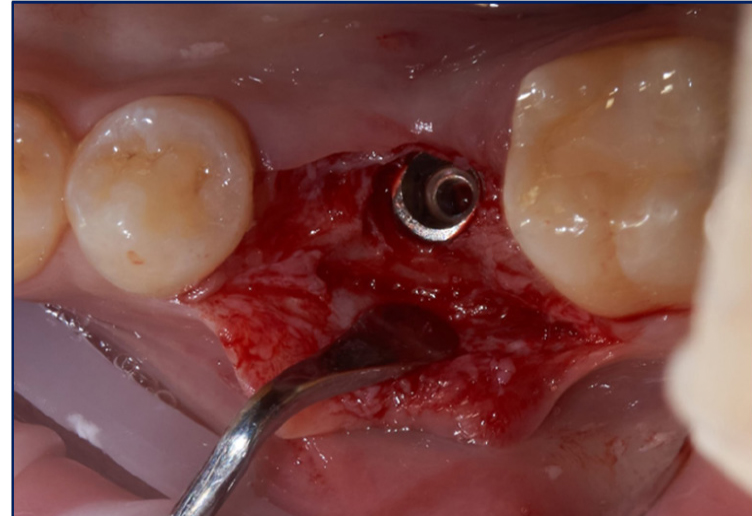

В ходе операции был реализован комбинированный лоскут, с расщепленной частью в апроксимальных и апикальных участках, с целью создания оптимальных условий для кератинизации, реваскуляризации и созревания используемого соединительно-тканного трансплантата. Платформа дентального имплантата (Osstem 4,5/10) спозиционирована субкрестально на 3 мм с целью компенсации вертикального дефицита мягких тканей для формирования биологической ширины (рис. 2).

Рис. 2. Субкрестальное позиционирование платформы дентального имплантата